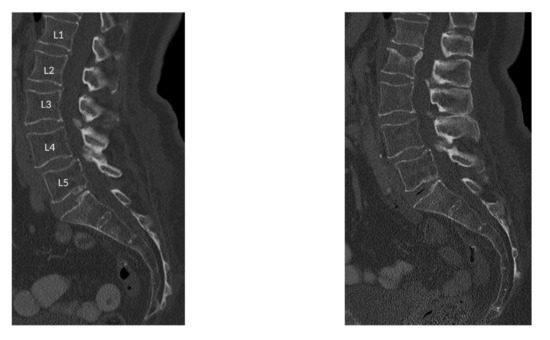

2.2. Image Acquisition